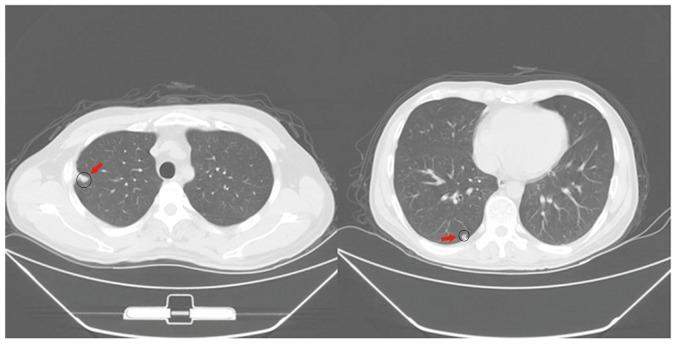

Although liver transplantation (LT) lengthens the survival time of patients with hepatocellular carcinoma (HCC), LT patients exhibit a high recurrence rate; particularly those that had advanced HCC associated with the tumor biological characteristics and long-term application of immunosuppressants. A consensus on optimal prophylaxis and treatment for recurrent HCC following LT does not currently exist. The present study retrospectively analyzed data from 36 non-University of California at San Francisco criteria-eligible patients with advanced HCC who underwent LT, and then treated them with sirolimus (SRL)-based therapy with thymalfasin and huaier granules (SRL+, n=18), or with tacrolimus-based therapy (controls; n=18). The SRL+ group had significantly longer recurrence times (P=0.008) and survival times (P<0.0001) (OS, 1-year: 100%, 3-year: 94.4%, 5-year: 77.8%; DFS, 1-year: 88.9%, 3-year: 55.6%, 5-year: 50.0%). Furthermore, compared with pre-LT values and the control group, the SRL+ group had significantly lower serum α-fetoprotein (AFP) levels (both P<0.0001) and percentage of Forkhead box P3 (FoxP3) Treg lymphocytes (P<0.001) during the first year. In the SRL+ group, FoxP3/cluster of differentiation (CD)8 Treg lymphocyte percentages decreased significantly following LT (P<0.001); however, CD8/CD3 T-cells significantly increased (P<0.001). Levels of serum AFP and FoxP3 Treg cells increased when tumors relapsed, and decreased to near-normal when relapse foci were cured or stabilized. SRL+ therapy may decrease AFP and Treg levels, while increasing CD8 T cells, indicating an associated mechanism among them. In conclusion, SRL+ therapy appears to be safe and effective in preventing HCC recurrence following LT with no significant adverse events, and warrants further investigation.

尽管肝移植(LT)可延长肝细胞癌(HCC)患者的生存时间,但肝移植患者的复发率很高;尤其是那些患有与肿瘤生物学特征相关的晚期HCC且长期应用免疫抑制剂的患者。目前对于肝移植后复发性HCC的最佳预防和治疗尚无共识。本研究回顾性分析了36例不符合加利福尼亚大学旧金山分校标准的晚期HCC患者接受肝移植的数据,然后对他们采用基于西罗莫司(SRL)的疗法联合胸腺肽α1和槐耳颗粒进行治疗(SRL+组,n = 18),或采用基于他克莫司的疗法(对照组,n = 18)。SRL+组的复发时间(P = 0.008)和生存时间(P < 0.0001)显著更长(总生存期,1年:100%,3年:94.4%,5年:77.8%;无病生存期,1年:88.9%,3年:55.6%,5年:50.0%)。此外,与肝移植前的值及对照组相比,SRL+组在第一年时血清甲胎蛋白(AFP)水平(均P < 0.0001)和叉头框蛋白P3(FoxP3)调节性T淋巴细胞百分比(P < 0.001)显著更低。在SRL+组中,肝移植后FoxP3/分化簇(CD)8调节性T淋巴细胞百分比显著降低(P < 0.001);然而,CD8/CD3 T细胞显著增加(P < 0.001)。肿瘤复发时血清AFP和FoxP3调节性T细胞水平升高,而复发灶治愈或稳定时降至接近正常水平。SRL+疗法可能会降低AFP和调节性T细胞水平,同时增加CD8 T细胞,表明它们之间存在相关机制。总之,SRL+疗法在预防肝移植后HCC复发方面似乎安全有效,且无明显不良事件,值得进一步研究。